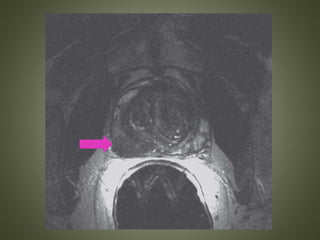

CRITERIA FOR EXTRACAPSULAR SPREAD

• Direct visualization of tumor extension

• Asymmetry or envelopment of the

neurovascular bundle

• Angulated prostate contour

• Irregular or spiculated prostate margin

• Retracted capsule

• Obliteration of the rectoprostate angle.

SEMINAL VESICLE INVASION

• Loss or disruption of the normal seminal vesicle

architecture

• Replacement of the T2-hyperintense seminal vesicle

with hypointense tumor

• Obliteration of the normal prostate–seminal vesicle

angle

ENDORECTAL COIL -MRI • The endorectal coil should be placed with the blue line oriented anteriorly and fixed in position with balloon inflation. • Scout localizer images are obtained in the axial and sagittal planes, and reviewed to ensure optimal positioning of the coil

• 67.

On axial localizerimages, the “ears” should be symmetrically positioned at the 10:00 and 2:00 positions such that signal from the coil is directly anteriorly

• 68.

On sagittal localizer images,the coil should be positioned to cover the prostate base superiorly and apex inferiorly.